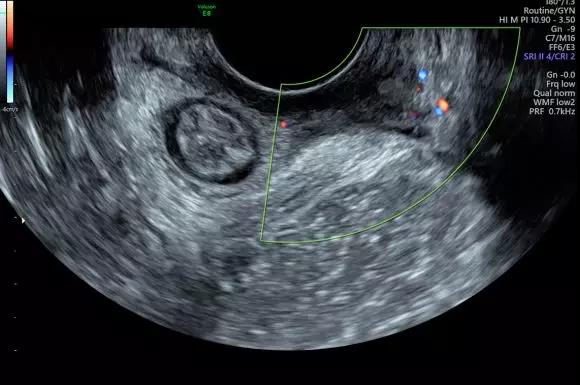

GE LOGIQ E9/S8及Voluson E8超聲儀

廣泛應用于腹部超聲、淺表超聲、肌骨超聲、血管超聲、心臟超聲、胃腸超聲等各種臨床應用,并具有腹部臟器超聲造影、淺表器官超聲造影功能,對腫瘤的良惡性鑒別具有較高診斷價值。

Voluson E8超聲儀:

廣泛應用于婦產超聲臨床領域,尤其在產科、不孕不育生殖醫(yī)學和女性盆底功能障礙性疾病等領域,提供高品質圖像及專業(yè)的婦產超聲臨床解決方案。

案例圖

女性不孕檢查

女性產后盆底功能檢查